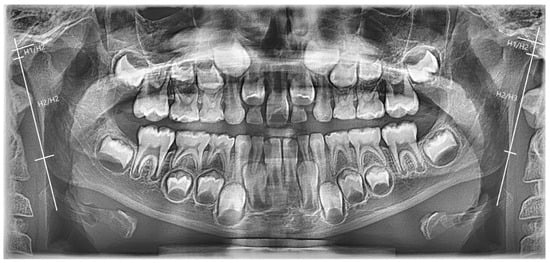

Case Description